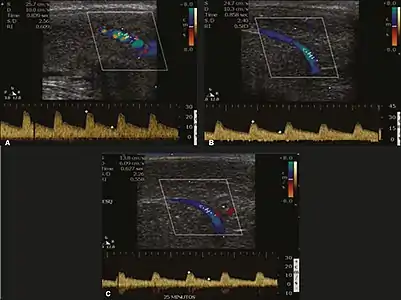

Penile ultrasonography with doppler can be used to examine the erect penis. Most cases of ED of organic causes are related to changes in blood flow in the corpora cavernosa, represented by occlusive artery disease (in which less blood is allowed to enter the penis), most often of atherosclerotic origin, or due to failure of the veno-occlusive mechanism (in which too much blood circulates back out of the penis). Before the Doppler sonogram, the penis should be examined in B mode, in order to identify possible tumors, fibrotic plaques, calcifications, or hematomas, and to evaluate the appearance of the cavernous arteries, which can be tortuous or atheromatous.[39]

Erection can be induced by injecting 10–20 µg of prostaglandin E1, with evaluations of the arterial flow every five minutes for 25–30 min (see image). The use of prostaglandin E1 is contraindicated in patients with predisposition to priapism (e.g., those with sickle cell anemia), anatomical deformity of the penis, or penile implants. Phentolamine (2 mg) is often added. Visual and tactile stimulation produces better results. Some authors recommend the use of sildenafil by mouth to replace the injectable drugs in cases of contraindications, although the efficacy of such medication is controversial.[39]

Before the injection of the chosen drug, the flow pattern is monophasic, with low systolic velocities and an absence of diastolic flow. After injection, systolic and diastolic peak velocities should increase, decreasing progressively with vein occlusion and becoming negative when the penis becomes rigid (see image below). The reference values vary across studies, ranging from > 25 cm/s to > 35 cm/s. Values above 35 cm/s indicate the absence of arterial disease, values below 25 cm/s indicate arterial insufficiency, and values of 25–35 cm/s are indeterminate because they are less specific (see image below). The data obtained should be correlated with the degree of erection observed. If the peak systolic velocities are normal, the final diastolic velocities should be evaluated, those above 5 cm/s being associated with venogenic ED.[39]